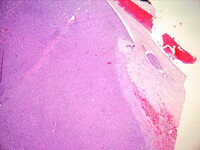

Histopathology of follicular carcinoma, thyroid

CDC Image Library/Dr Edwin P. Ewing, Jr